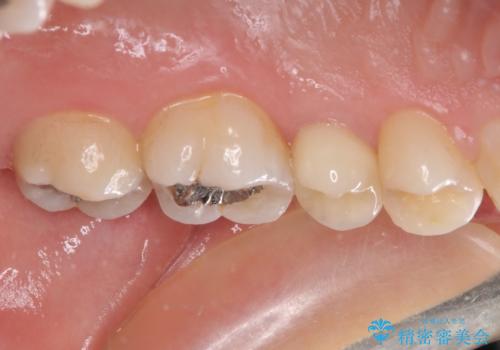

- 近医にてむし歯治療を行った後に痛みが出たとのことで来院された患者様です。

左下奥歯は術後から咬合時の痛みが発現し、来院時には脈を打つような痛みが認められました。

診察の結果、神経を取り除く必要があると判断されたため根管治療を行いました。

その後、左上の奥歯にも咬合時の痛みが認められ、レントゲン写真より歯内の神経が失活していることが分かりました。

2歯ともに根管治療を行い、その後はオールセラミッククラウンにて補綴治療を行うこととしました。